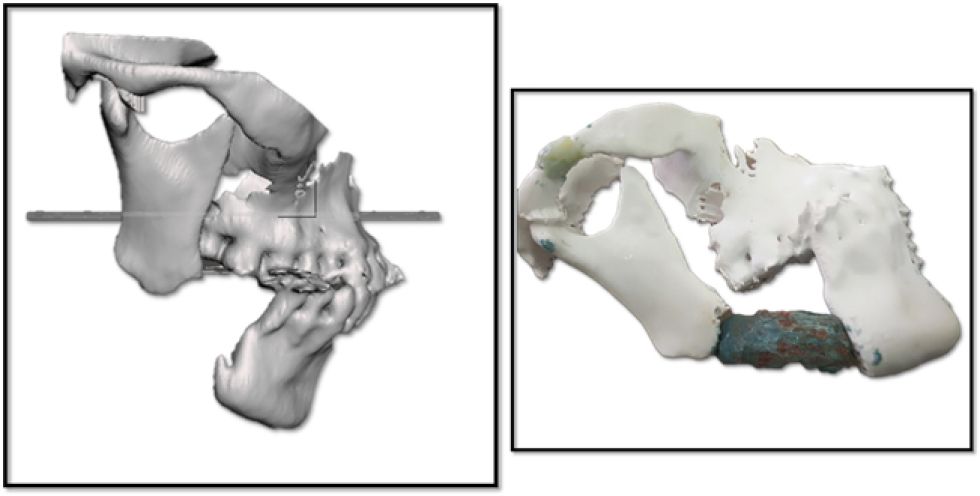

La tecnología y el uso de Software Libre permitió planificar la reconstrucción Mandibular antes de ingresar al quirófano

La tecnología y el uso de Software Libre permitió planificar la reconstrucción Mandibular antes de ingresar al quirófano Foto: Cedida

La tecnología permitió una reconstrucción en 3D sobre un modelo exacto como herramienta de planificación para los cirujanos.

La tecnología permitió una reconstrucción en 3D sobre un modelo exacto como herramienta de planificación para los cirujanos. Foto: Cedida

“La indicación era la reconstrucción mandibular con colgajo microvascularizado. Asumimos el reto sin haberlo hecho antes por la paciente, que era del SUS (Sistema Único de Salud)”, relata el doctor Aillón. La planificación se desarrolló mediante una cirugía virtual guiada con biomodelos digitales del peroné y la mandíbula, herramienta que permitió anticipar los cortes, definir el tamaño del injerto y diseñar las placas antes de entrar al quirófano.

La integración de la tecnología digital resultó determinante para reducir los márgenes de error y aumentar la seguridad. “Hicimos una cirugía guiada por computadora con software libre y biomodelos tridimensionales”, explica Aillón al destacar la precisión del procedimiento.